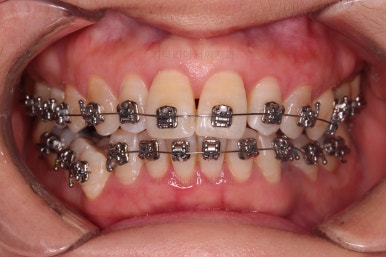

이번에 사용하신 장치는 엠파워 메탈이라고 하는 자가결찰 금속 장치인데요.

금속 재료를 시각적으로 신경쓰지 않으셔꼬 메탈장치가 세라믹에 비해 양치라던지 잇몸에 그래도 약간의 장점이 있어서 추천되기도 했어요.

비발치 치료에서 핵심되는 장치가 미니스크류에요.

위 사진에서도 어금니쪽 잇몸 부위를 보시면 아주 작은 금속성 나사머리가 보이실건데요. 나사로 단단히 지탱해주고 치열을 뒤로 당겨주는 원리죠.

치료의 막바지인데도 불구하고 아직 앞니쪽에 틈이 보이죠?

틈새는 가장 마지막에 모이게 될거에요.